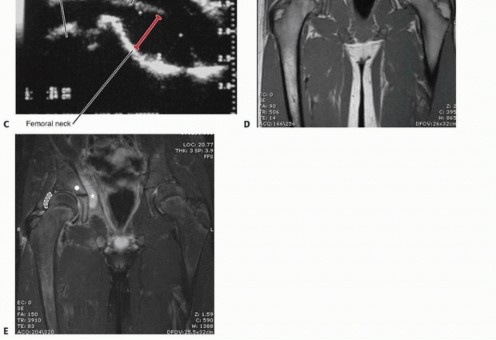

FIG 3

•

(continued)

F.

T1-weighted coronal image with gadolinium for enhancement. Cavitary nature of the abscess (

asterisk

) is even more apparent. Patient underwent percutaneous interventional radiology catheter drainage on two occasions and received intravenous antibiotics for treatment of this methicillin-sensitive

Staphylococcus aureus

infection.